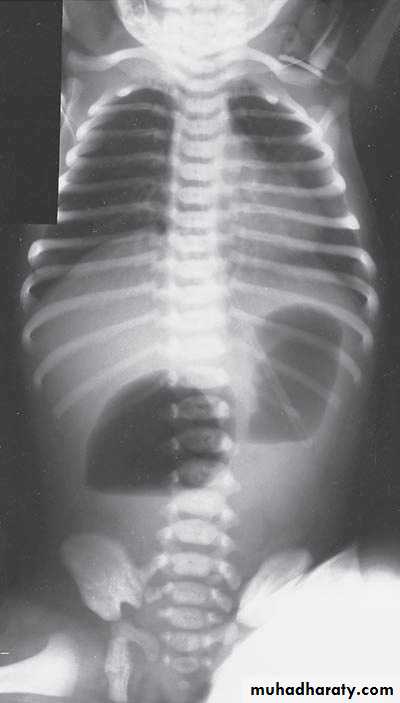

Bowel Obstruction